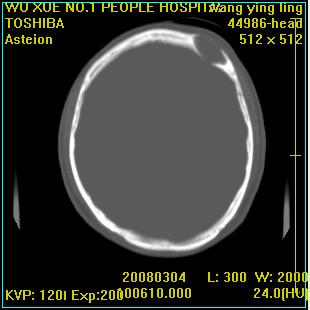

标题: CT12023:女,50岁,头部包块二月,伴轻微头痛,不伴发热。 [打印本页]

标题: CT12023:女,50岁,头部包块二月,伴轻微头痛,不伴发热。

这种病例还是比较多见,起源于颅骨板障,向颅内和颅外生长,考虑血管瘤或嗜酸性肉芽肿,要是有增强ct就好了。

多发溶骨性破坏,骨嗜酸性肉芽肿可能,转移瘤待排除,建议进一步检查。

破坏区边界较清楚,还是考虑良性病变---嗜酸性肉芽肿可能。

病灶呈溶骨性骨破坏,考虑嗜酸性肉芽肿可能转移瘤不除外建议追查病史并进一步检查